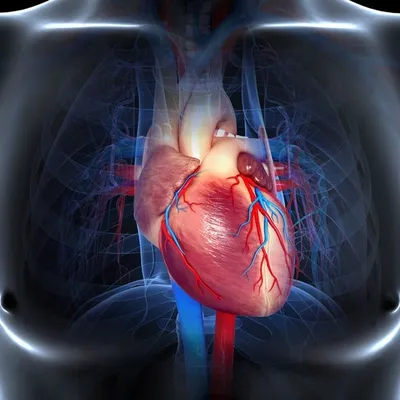

NO Circulation?

No Circulation is the term used in first aid when a person has stopped breathing. The heart is no longer pumping blood around the body.

- Heart failure